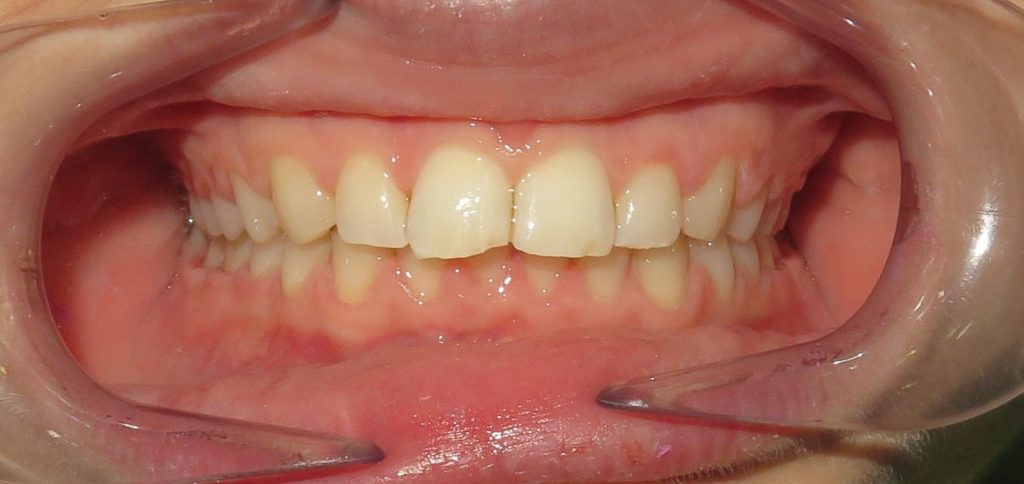

Pod opieką Agnieszki Łukowicz, Master of Science Orthodontics została poddana zaawansowanemu leczeniu aparatem stałym ligaturowym, Dzięki czemu udało się osiągnąć znaczące zmiany:

poszerzenie luków zębowych,

korekta tyłozgryzu,

rozwiązanie stłoczenia,

odrotowanie zrotowanych zębów,

odbudowa startych zębów.

Efekt estetyczny został dopełniony przez wybielanie zębów i odbudowę kompozytową wykonaną przez dr Monikę Niewitecką.

Przedstawiamy piękny i zdrowy uśmiech naszej Pacjentki!